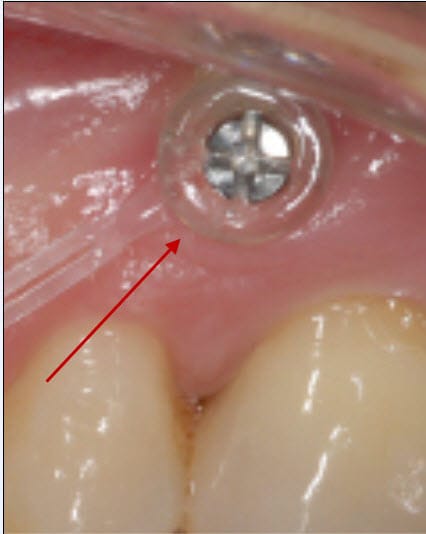

En employant le mot de collerette, je ne parlais pas de la chaînette élastomérique qu'on voit très bien sous tension, mais de ce qui paraît être un anneau en plastique transparent qui cercle la tête de vis. Qu'est-ce que c'est ?

Je remets la photo.

@ Dancha: les collerettes j'ai eu l'impression qu'elle les a enlevé pour les remettre une fois les chaînettes installées...p'tètre juste pour protéger?

Je pense effectivement que ce sont des protections pour limiter le risque d’irritation jugale par les têtes de vis.

Dans ton cas, il serait sans doute souhaitable que tu les fasses enlever pour pouvoir nettoyer plus facilement la jonction muqueuse des vis et limiter au maximum le risque inflammatoire.